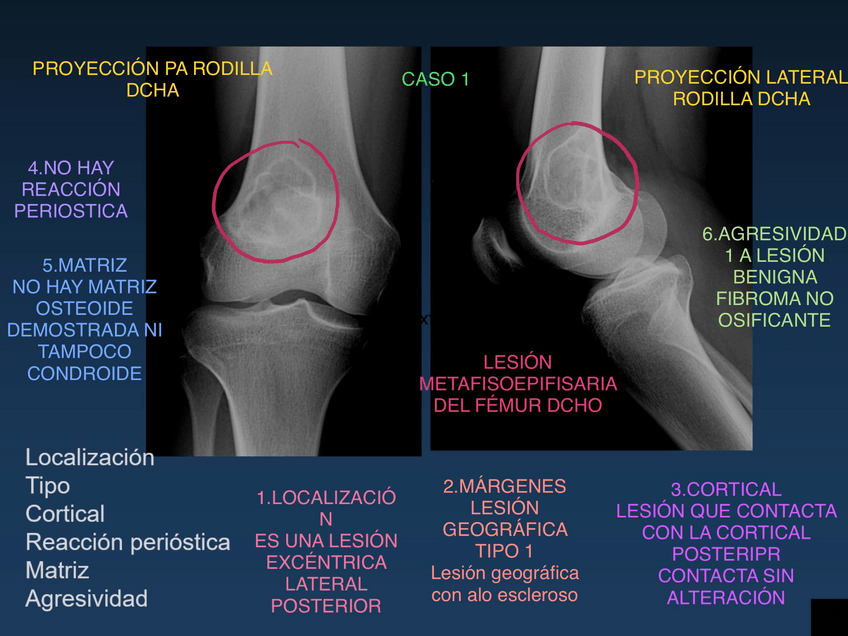

He publicado nuevos practicas de 2º Radiologia General: Practicas-Radiologia.-MSK.pdf

Practica-musculoesqueletico.pdf